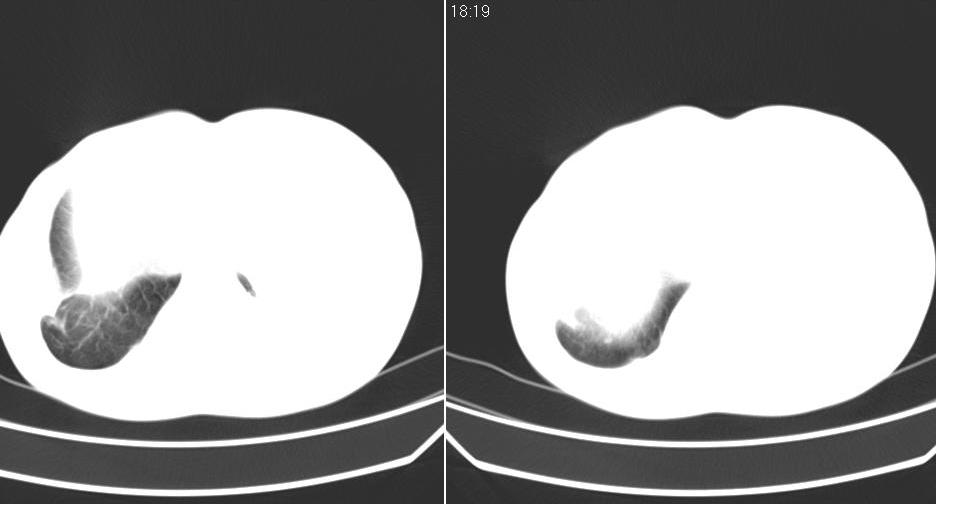

以下是引用苯小孩在2007-6-27 15:09:00的发言:[br]考虑:1、右肺继发性肺结核.2、双侧包裹性积液<胸腔及叶间>3、双侧局部胸膜增厚.[br]建议胸水化验检查.

以下是引用yanghaochen88在2007-6-27 15:08:00的发言:[br]双肺上野散在粟粒状影、包裹性积液、胸膜增厚粘连、叶间积液---tb,至于分型还得结合病史体征细究妥当些。